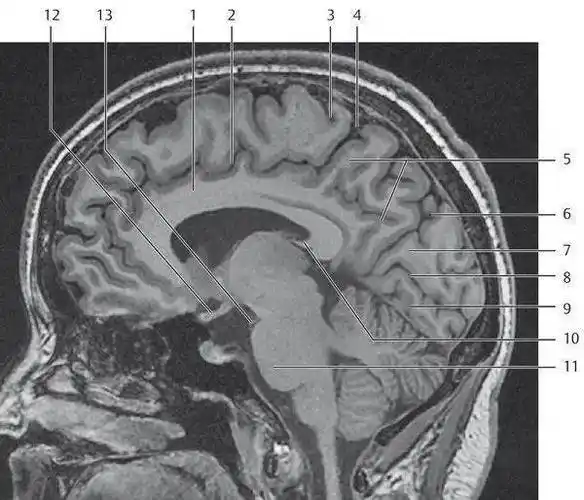

341头部磁共振解剖

312.头部磁共振影像解剖

完整的头颅mri解剖 ,值得收藏!